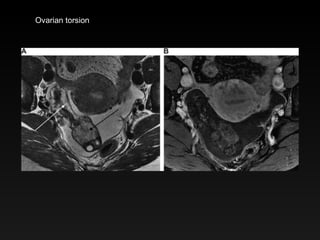

Ovarian torsion

Copyright ©Radiological Society of North America, 2007 Singh, A. et al. Radiographics 2007;27:1419-1431 Adnexal torsion

Copyright ©Radiological Societyof North America, 2007 Singh, A. et al. Radiographics 2007;27:1419-1431 Adnexal torsion